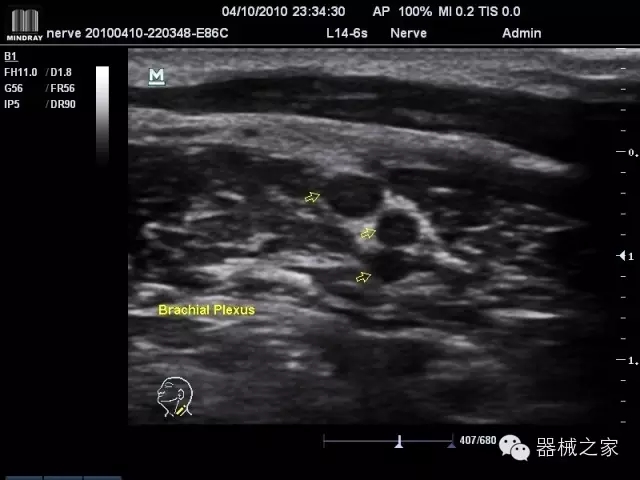

臨床圖片賞析

產(chǎn)品特點(diǎn)

·優(yōu)秀的圖像效果、強(qiáng)大的功能體驗(yàn)、豐富的探頭選擇、合理的便攜式設(shè)計(jì),全中文顯示及病人管理界面,使得M7在任何場(chǎng)合、任何時(shí)候都能快速響應(yīng)更好的心血管、腹部、婦產(chǎn)、小器官等常規(guī)超聲檢查以及肌骨、神經(jīng)、顱腦、術(shù)中等新興領(lǐng)域的使用需求;